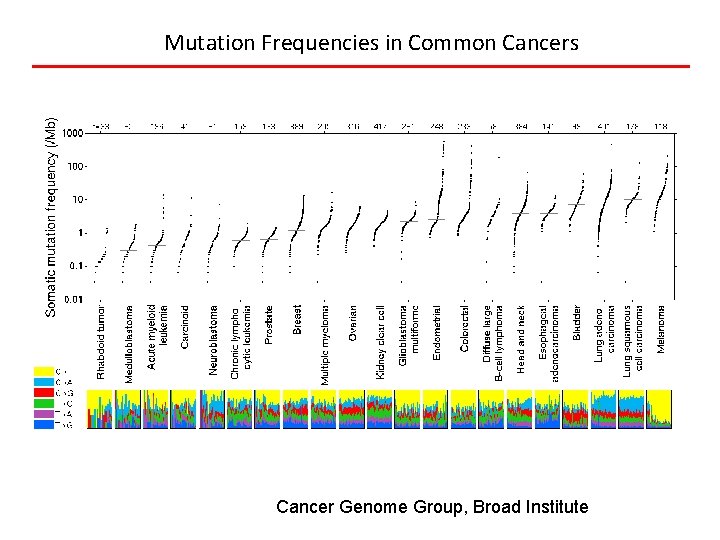

Types of Mutations • Driver mutation: directly responsible for promotion of tumor growth (can be oncogene of tumor suppressor) and good target for drug development. Thought to be approximately 10 per tumor. Point mutations, amplifications and gene fusions. • Passenger mutation: occur randomly through genome due to DNA repair defects in tumor cells and do not contribute to cell growth. Thousands per lung cancer genome.

Mutation Frequencies in Common Cancers Cancer Genome Group, Broad Institute

Neo-antigen Hypothesis • Neo-antigens are mutant proteins in cancer (10 s to 1000 s per cell), and can be catalogued by DNA sequencing • Are seen as foreign proteins and cells expressing them are attacked, except…. • Tumor cells have co-opted the normal tolerance mechanisms used to avoid autoimmunity (checkpoints) • Immunotherapy works because of tolerance blockers or neoantigen-specific T cells or vaccines Schumacher and Schreiber, Science 2015